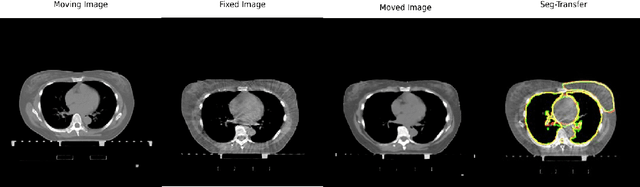

Abstract:We propose a flow-based registration framework of medical images based on implicit neural representation. By integrating implicit neural representation and Large Deformable Diffeomorphic Metric Mapping (LDDMM), we employ a Multilayer Perceptron (MLP) as a velocity generator while optimizing velocity and image similarity. Moreover, we adopt a coarse-to-fine approach to address the challenge of deformable-based registration methods dropping into local optimal solutions, thus aiding the management of significant deformations in medical image registration. Our algorithm has been validated on a paired CT-CBCT dataset of 50 patients,taking the dice coefficient of transferred annotations as an evaluation metric. Compared to existing methods, our approach achieves the state-of-the-art performance.